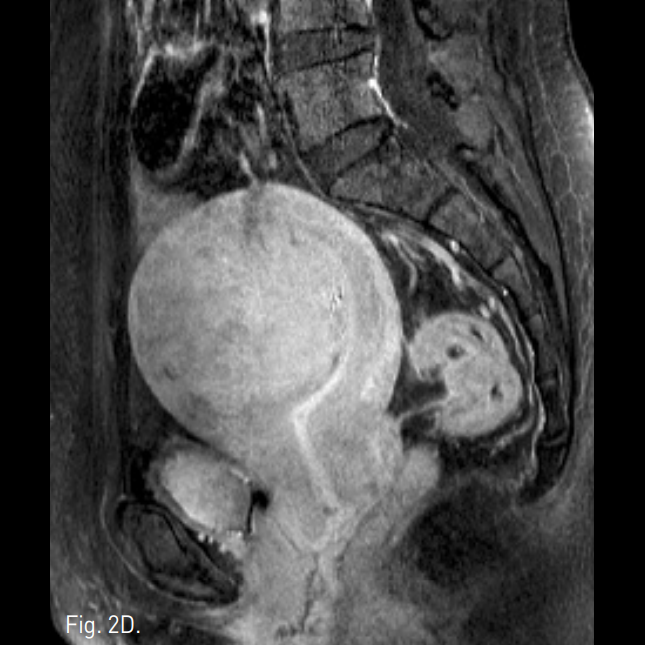

Fig. 2

A-C. T2-weighted transverse (A), coronal (B), and sagi ttal (C) MR images show a huge mass of low signal intensity.

D. T1-weigh ted MR image with contrast enhancement shows a homogeneous enhancing mass.